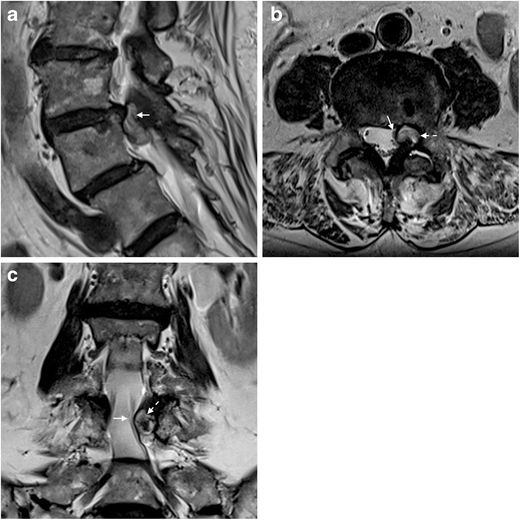

腰痛难忍椎小关节滑膜囊肿